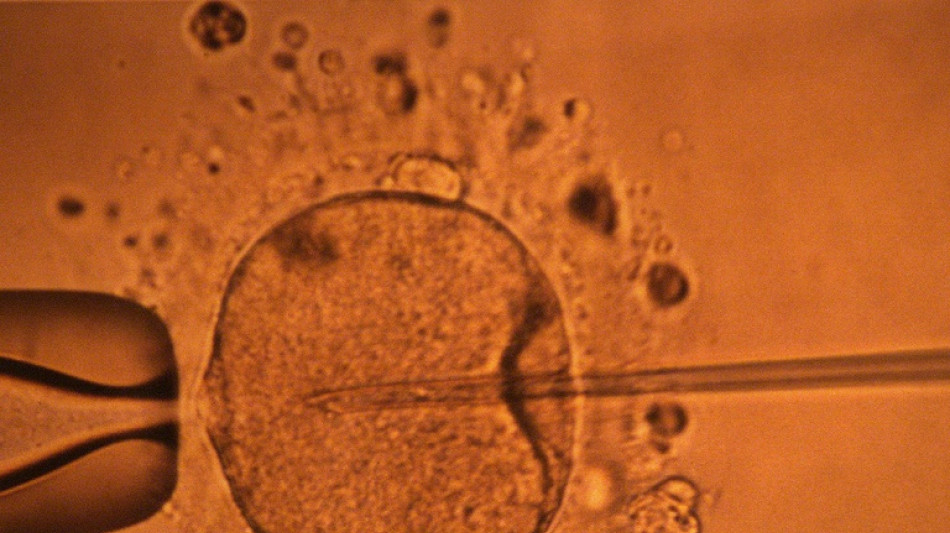

Une étude appuie l'hypothèse d'un déclin mondial de la concentration en spermatozoïdes / Photo: © AFP/Archives

La concentration en spermatozoïdes, l'un des facteurs de la fertilité masculine, a nettement baissé à travers toute la planète au cours des dernières décennies, avance une vaste étude publiée mardi.

"La concentration en spermatozoïdes a sensiblement diminué entre 1973 et 2018", résument les auteurs de ce travail, paru dans la revue Human Reproduction Update et réalisé en compilant une quarantaine d'études préalables.